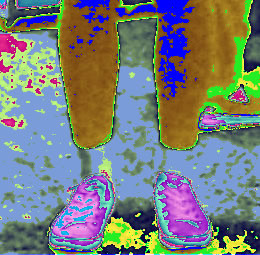

This picture shows damage to the bones in the hand.

This picture shows damage to the bones in the hand.  This picture shows infected sinuses.

This picture shows infected sinuses.  This picture shows poor blood flow to the lower legs.

This picture shows poor blood flow to the lower legs.  This picture shows problems with the heart and a problem with the brain due to mechanical injury.

The pictures show the camera in operation, the before and after pictures.

Before ERIC mode  During ERIC mode (no radiation).

During ERIC mode (no radiation).